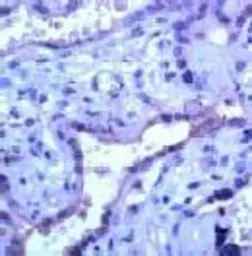

MMP23 antibody (ready-to-use)

Cat. No. GTX15479

ApplicationsIHC-P

ReactivityHuman